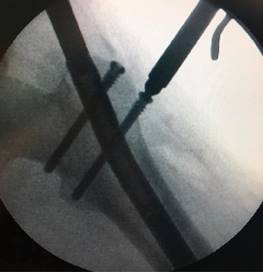

Se identificó el lugar de la osteotomía femoral siguiendo el método habitual descrito por Paley y colaboradores,13 realizándose mediante múltiples perforaciones a través de un abordaje lateral. Como describen algunos autores, estas perforaciones registran una baja tasa de tromboembolismo pulmonar.2 El punto de entrada del clavo se realizó en la punta del trocánter mayor a través de un abordaje lateral proximal (Figura 1), que permitió el fresado del canal femoral hasta 1.5-2 mm mayor que el diámetro definitivo del clavo seleccionado. Se introdujo el clavo intramedular Precice® hasta el borde proximal de la zona de osteotomía y se completó la misma a través del abordaje lateral, introduciendo el clavo hasta su localización definitiva y bloqueándolo proximal y distalmente (Figura 2). Por último, se realizó la distracción del clavo 1-2 mm para asegurar el correcto funcionamiento del dispositivo magnético.